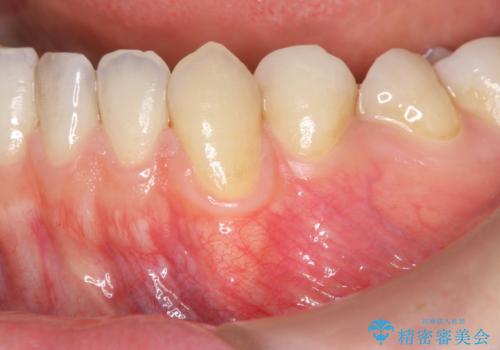

- 歯茎の下がりが気になる 歯肉移植でさがりにくくする- 担当医 井上季実子